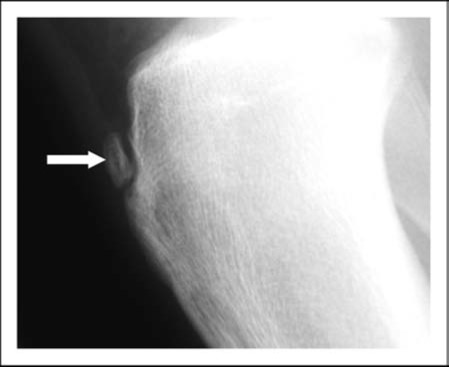

病院でレントゲンを撮影したところ、下のような状態でした。

膝の前面に骨片が存在していました。「ジャンプの際に急に痛みが出た」という部分に着目すると、これはジャンプの大きな力によって生じた「スポーツ外傷」と考えられます。

しかし、たかが一回のジャンプの衝撃だけで、骨折してしまうのでしょうか?

やはり実際の話は単純ではありません。実は、この男の子は元々オスグッド病と呼ばれる「スポーツ障害」を抱えていました。

成長期において、骨の成熟が完了していない為、ジャンプなどの負荷が加わり続けると、膝のお皿の下の靭帯(膝蓋靭帯)に骨が牽引される負担がかかり続け、徐々に炎症や骨の変形が生じます。

この選手は元々スポーツを続ける中で、慢性的に骨に負担が加わり続けていました。